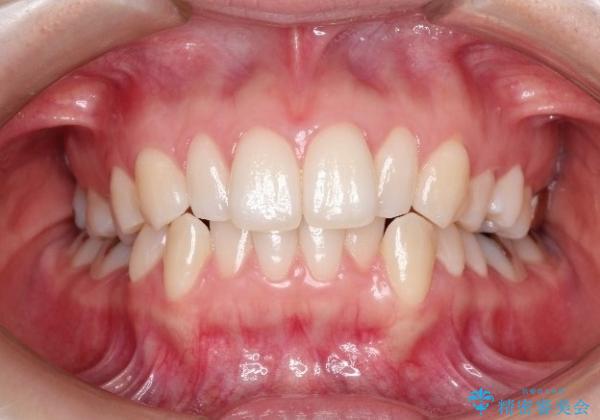

初診時の歯並びの状態としては、上下ともに前歯部の中等度のがたつきがあり、特に左上の前歯が1本内側に入り込んでしまっている状態でした。

また、2mm程度の正中離開がありました。